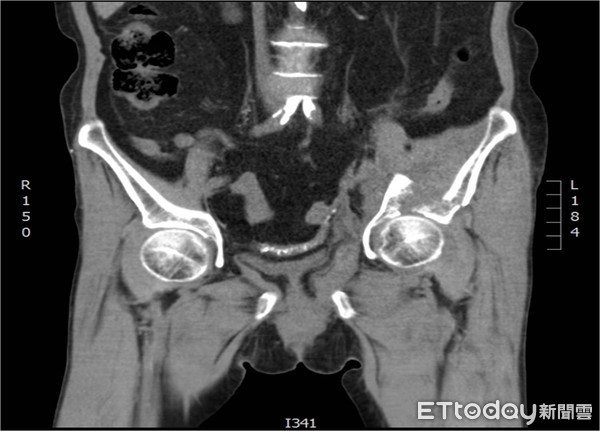

衛福部彰化醫院骨質疏鬆症專科醫師陳柏辰表示,患者經X光與電腦斷層檢查,發現為罕見且嚴重的髖臼骨折,且為最嚴重的「雙柱骨折合併中心脫位」,這類傷勢通常發生在高處墜樓或遭車輛高速撞擊,但該婦的骨質密度T值-3.4,比起骨鬆定義值-2.5低了不少,如此脆弱的骨質,導致輕輕一摔就骨折嚴重。

▲電腦斷層顯示嚴重髖臼骨折。(圖/彰化醫院提供)

陳柏辰說,此類骨折病患通常需要髖臼前後方兩次手術復位加上鋼板固定,手術時間長且流血多,但婦人近期才因心臟衰竭合併肺水腫住院,並不適合接受如此重大的手術,加上骨鬆嚴重,若打上鋼板,猶如將房子蓋於沙堆上,並不適宜,因此決定不動手術,採取牽引治療,再於肚皮打入強效的長骨針,一併治療嚴重的骨折與骨質疏鬆。